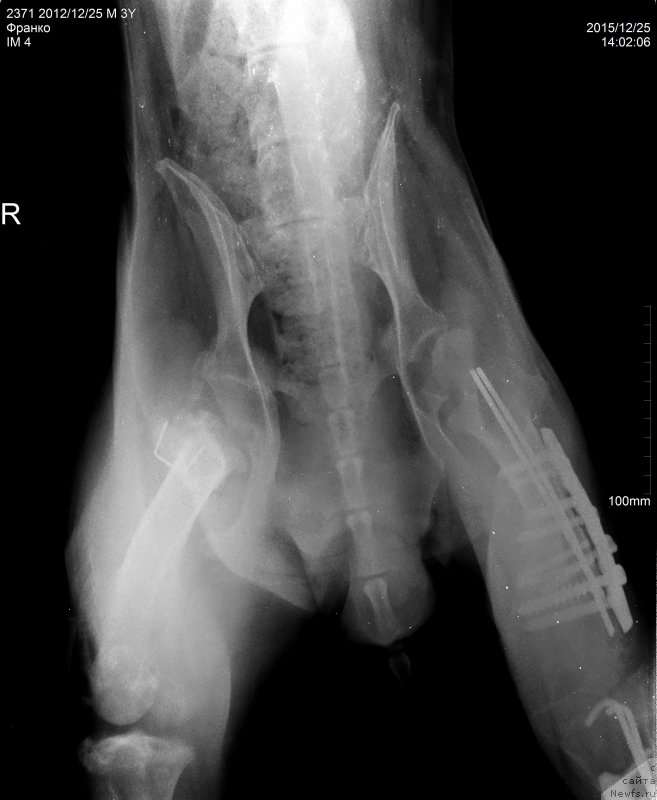

2015.12.25.=Франко снимки таз ВД

Фотография № 198292

ФРАНКО испанский мастиф болен с рождения(наружный подвывих головок тазобедренных костей в обоих суставах,вторичная дисплазия тазобедренных суставов за счёт слабости связачного аппарата и диффузного остеопороза)

Сергей Александрович написал что абсцесс в мягких тканях а не в надкостнице, как нам озвучили на рентгене.

Ну и артроз коленного сустава.

Артроз у Франко ужаснейший.

Хуже мне кажется уже и быть не может.

Ноги Франко так устроены, что он сам их разбивает.

Это чудо , что он еще на ногах,

Нужно чтоб пластины стояли как можно дольше.

Чудо, что Франко на ногах, радуйтесь каждому месяцу.

Это нам написала наша врач.